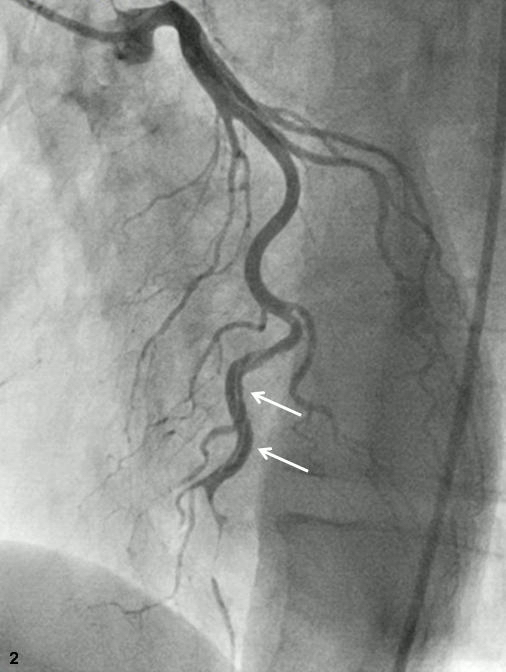

Abstract PDF ECG 1 Angio 1 Angio 2 Angio 3 Angio 4 ECG 2 Table Chart Original File 1 2 3 4 5 6 Reply to reviewer Fig. 1. ECG during myocardial infarction Fig. 2. Coronary angiography of LCA during myocardial infarction Fig. 3. Coronary angiography of LCA during myocardial infarction Fig. 3a. Coronary angiography of LCA during myocardial infarction Fig. 4. Coronary angiography of LCA 2 years after myocardial infarction Fig. 5. Coronary angiography of LCA 2 years after myocardial infarction Fig. 6. ECG 2 years after myocardial infarction Fig. 7. Thrombolytic trials in patients with coronary artery dissection Fig. 8. Flow chart of the study selection process -